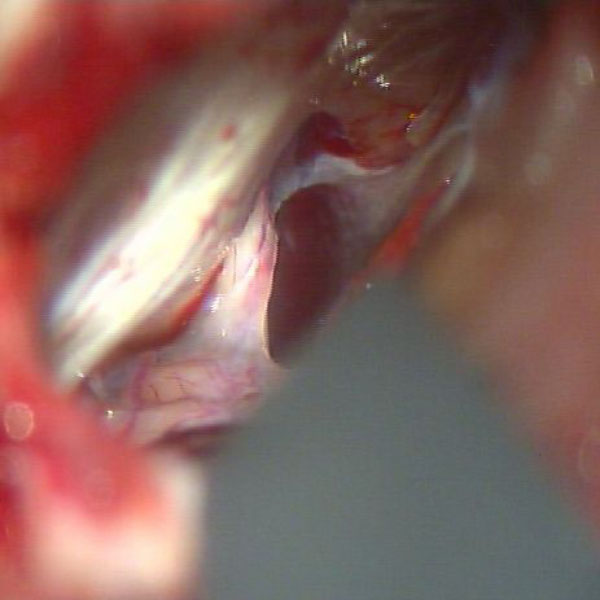

手術中

処置前

処置後